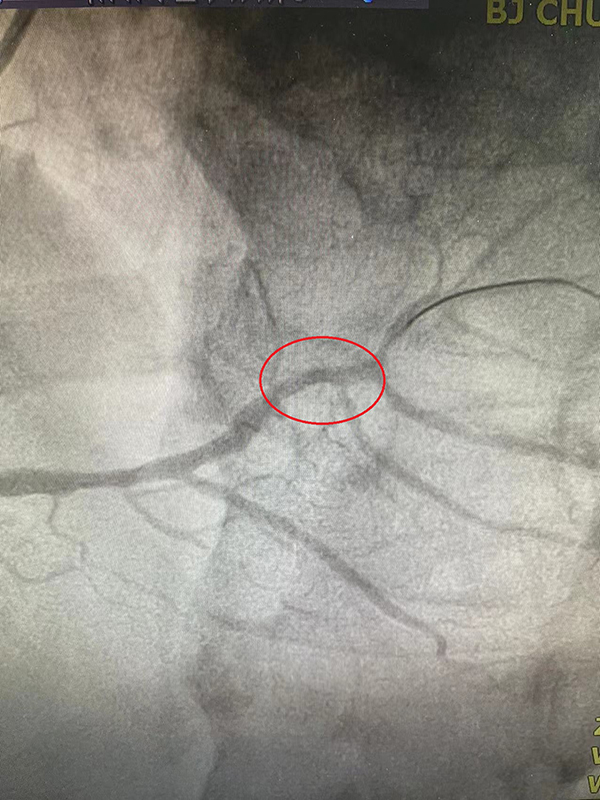

右冠脉原支架通畅,中远段50%节段性狭窄,左室后支近段95%局限性狭窄